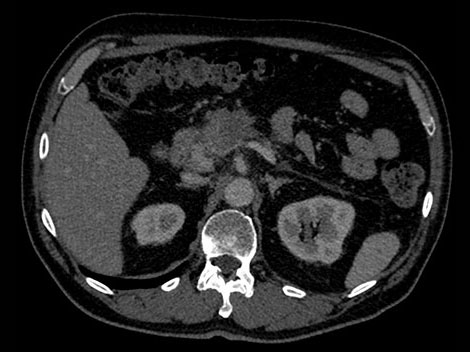

In this hypothetical example, the radiologists need more information about a visible mass in the pancreas in order make a confident diagnosis.

Unlike traditional CT images, spectral-detector CT images capture spectral information 100% of the time —without special planning or set-up. That means you can analyze the spectral data in any image retrospectively, using a variety of spectral viewing tools. You can, for example, adjust the monoenergetic level or get Zeffective maps. Try it yourself below.

Spectral-detector simultaneously absorbs and differentiates high and low energy from a single polyenergetic X-ray beam. Spectral results are acquired within a single scan without the need for special modes.